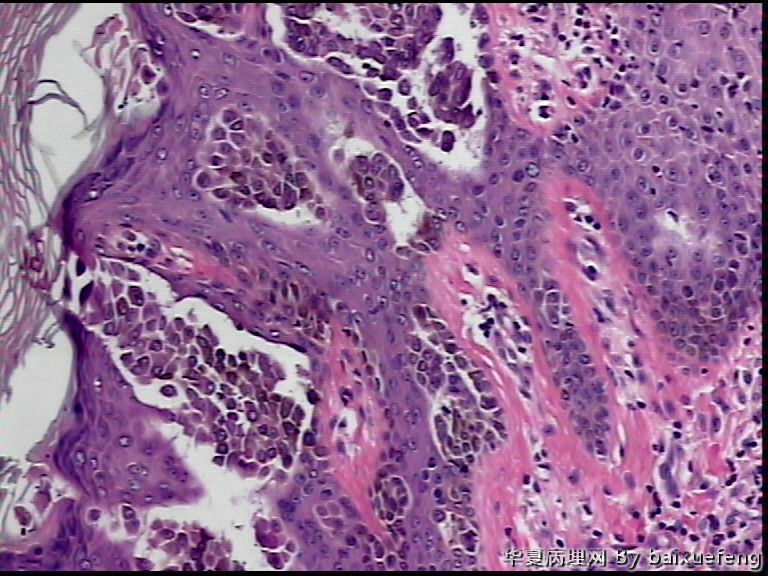

患者 女性 发现腰部皮肤肿物月余,表面0.5灰褐色结节

图1*40

图2*100

图3*100

图4*200